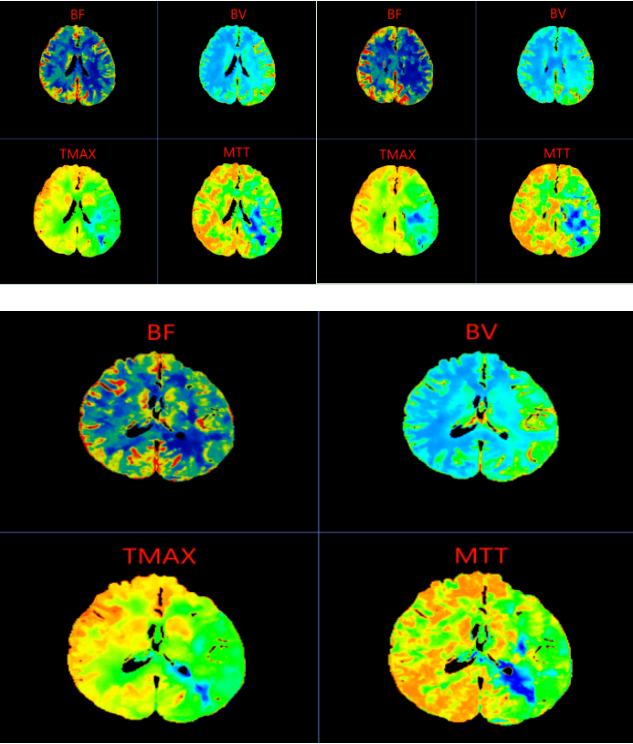

图像中,颜色映射左侧大脑半球显示局部脑血流量(CBF)下降,而脑血容量(CBV)可能基本正常或轻度升高,提示脑血管正在代偿性扩张以维持供血,但已濒临失代偿边缘。